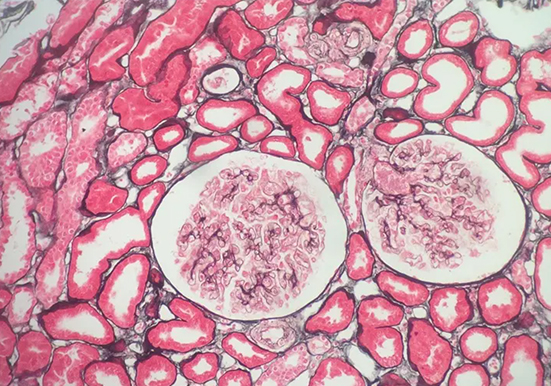

刚果红染色

刚果红染色是一种常用的生物染色方法,以下是关于它的详细介绍:基本信息染料性质:刚果红是一种经典的酸性染料,化学式为 C32H22N6Na2O6S2,是一种棕红色粉末,能溶于水和乙醇。染色原理:主要依赖于其与蛋白质及其他生物大分子的亲和性,通过静电吸引、氢键等作用力与样品中的不同组分发生相互作用,使样品呈现出特定的颜

染色原理:主要依赖于其与蛋白质及其他生物大分子的亲和性,通过静电吸引、氢键等作用力与样品中的不同组分发生相互作用,使样品呈现出特定的颜色。

染色:将切片放入刚果红工作液中染色 10min,然后用流水冲洗 1min。

分化:将切片放入碱性乙醇溶液中分化 1-3s,再用流水冲洗 1min。

复染:常用苏木精进行复染,将切片放入苏木精染液中染色 2min,然后用流水冲洗 1min。